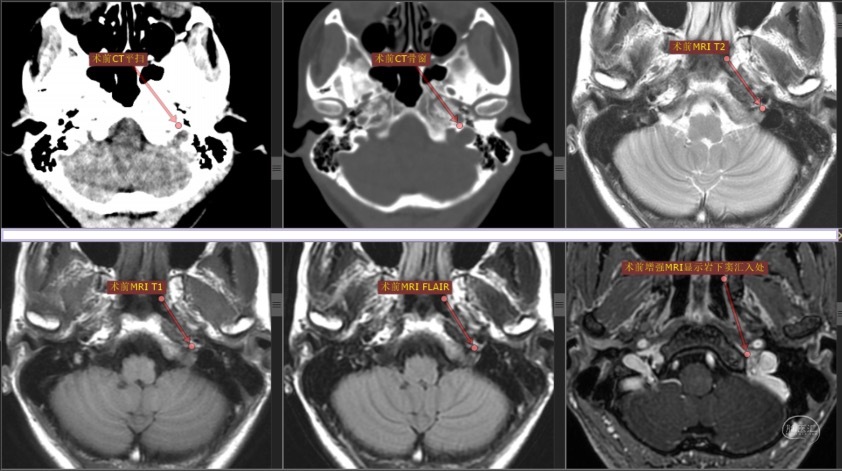

患者青年女性,因“发音嘶哑7年,左颈肩部肌肉萎缩4年”入院。既往体健,查体显示声音嘶哑,左侧胸锁乳突肌和斜方肌明显萎缩。肌电图示左侧胸锁乳突肌、斜方肌、冈上肌和菱形肌神经源性受损。头颅磁共振平+增强检查提示“脑内多发缺血灶;松果体小囊肿;颈静脉孔区未见明显占位性病变”。

根据患者症状和体征,排除肺部病变,考虑病变定位于左侧颈静脉孔区导致左侧第Ⅹ和第Ⅺ颅神经同时受累。尽管磁共振报告“阴性”,但我们从术前CT和磁共振影像上仔细观察,还是能发现一些蛛丝马迹:CT显示左侧颈静脉孔较对侧略扩大,磁共振增强扫描显示左侧岩下窦汇入颈静脉孔处有不均匀增强信号。